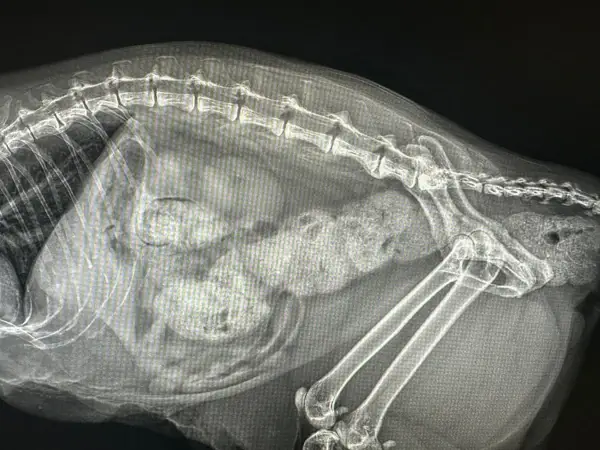

Diagnóstico por Imagen: Radiología y Ecografía

El diagnóstico por imagen es fundamental en medicina felina moderna. Muchas enfermedades solo pueden diagnosticarse mediante visualización directa de órganos internos, y la capacidad de obtener imágenes de alta calidad determina la precisión del diagnóstico.

Radiología digital: Nuestro equipo de rayos X digital proporciona imágenes de alta resolución en segundos, con una fracción de la radiación de los sistemas analógicos tradicionales. Esto es especialmente importante en gatos, donde la exposición debe minimizarse por su menor tamaño corporal.

La radiografía es insustituible para:

- Evaluación de patología respiratoria (neumonía, asma, efusión pleural)

- Diagnóstico de cardiomegalia y valoración de silueta cardíaca

- Detección de fracturas, displasias y artropatías

- Localización de cuerpos extraños radiopacos

- Evaluación de patología abdominal (obstrucción intestinal, organomegalia)

Realizamos estudios radiográficos con sedación mínima o sin sedación cuando es posible, priorizando el bienestar del paciente. En casos donde se requieren múltiples proyecciones o posiciones específicas, utilizamos sedación leve para evitar estrés y garantizar la calidad de las imágenes.

Ecografía abdominal y cardíaca: La ecografía es una técnica no invasiva que permite visualizar órganos internos en tiempo real, evaluando su estructura, tamaño y vascularización. A diferencia de la radiografía, no utiliza radiación y proporciona información sobre la arquitectura interna de los órganos.

La ecografía abdominal es especialmente útil en el diagnóstico de enfermedad renal crónica, permitiendo evaluar el tamaño, la ecogenicidad y la arquitectura renal. Podemos detectar quistes, cálculos renales, hidronefrosis y cambios estructurales indicativos de daño renal antes de que aparezcan síntomas clínicos.